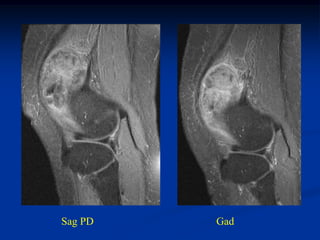

CLASSIC Case #279 Sagittal T-1 MRI 63 year female with myxolipoma knee

• 121.